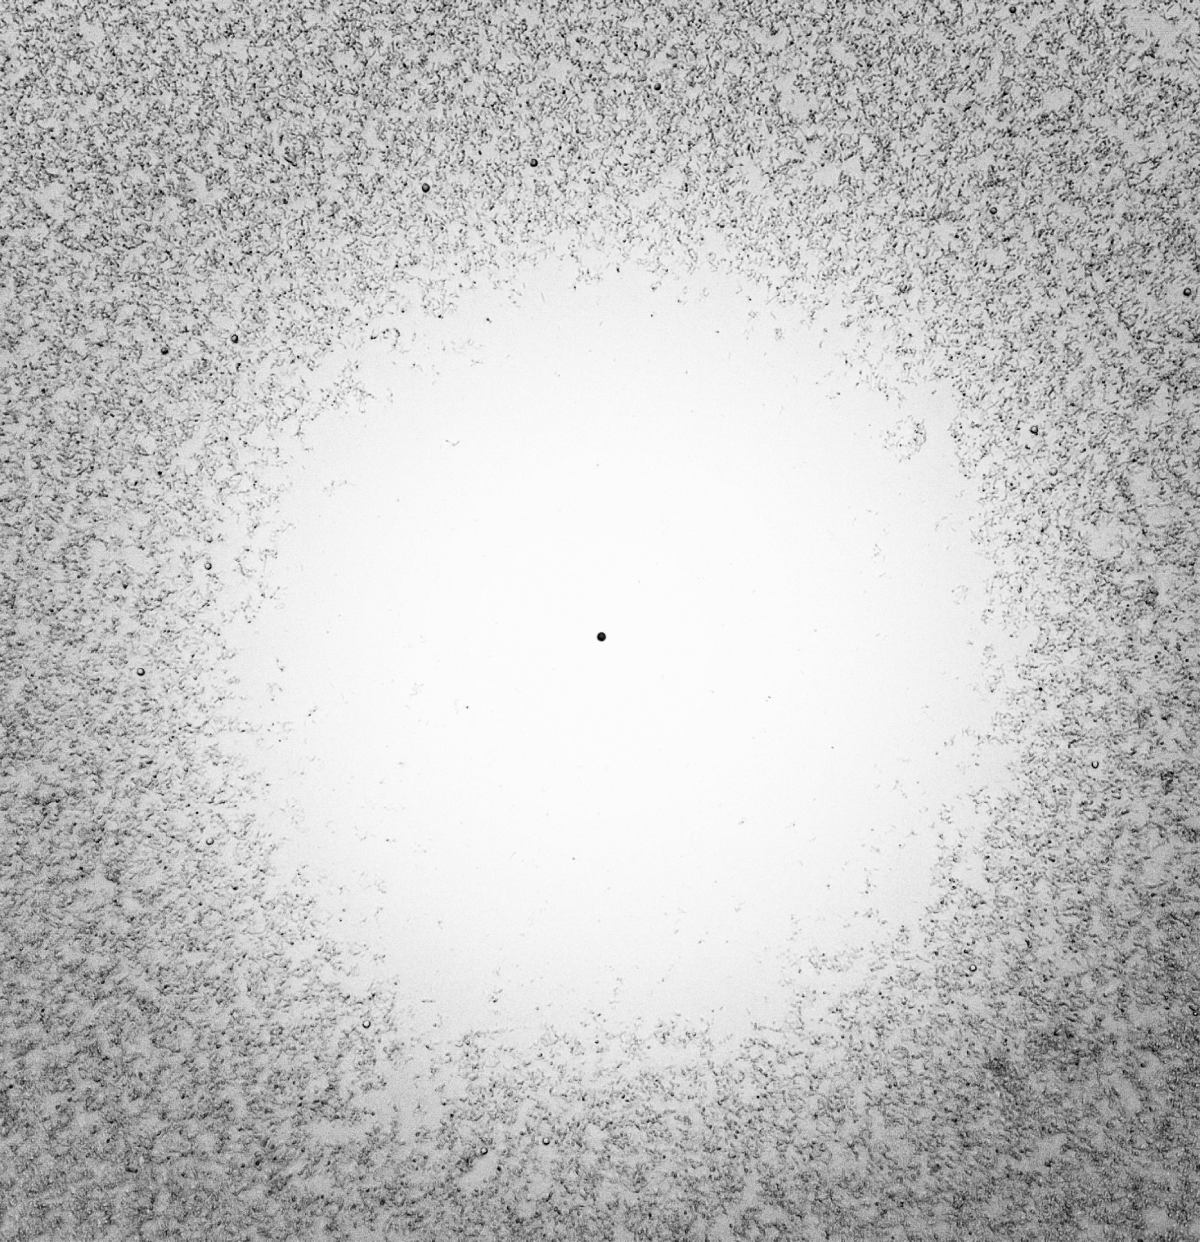

Mtb

We generate and functionally select antibodies directed to the surface of the Mtb with the aim of inhibiting the growth of the bacterium, or killing it. Such antibodies block specific secreted virulence factors; a fundamental enzymatic function; or they rely on immunological effector functions of the host.

Austrianni generated and characterized the largest collection worldwide of monoclonal antibodies directed against a plethora of Mtb antigens. To help limit the spread of this potentially deadly disease, we use our antibodies to develop fast and reliable diagnostics for point-of-care and clinical testing.